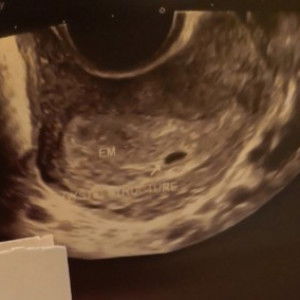

Dreaming of becoming a parent